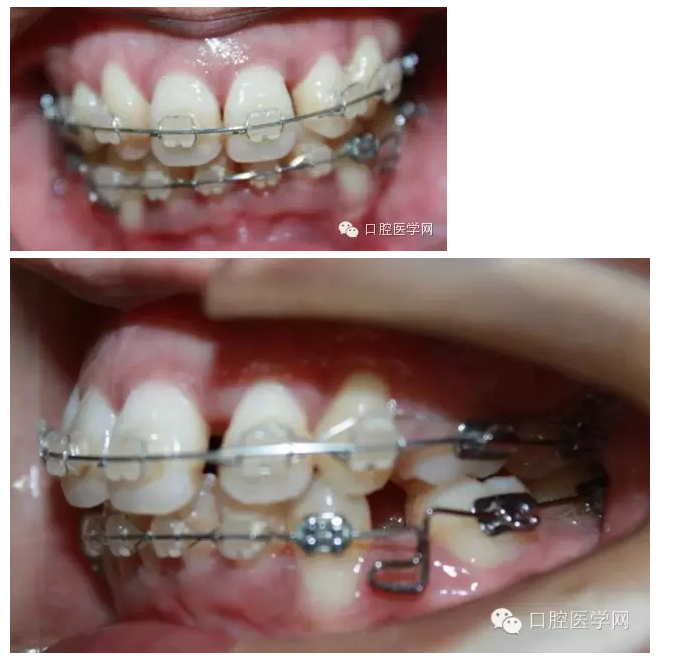

排齊后,我用搖椅方鈦絲壓低下前牙,結(jié)果一個(gè)月之后,牙齒基本上沒(méi)有什么變化,弓絲變得平直。之后再試了一次,也幾乎沒(méi)有效果。因?yàn)榛颊叩腟pee曲線太深了。

之后我換用0.018x0.025不銹鋼絲,在33,43遠(yuǎn)中彎制水平曲,階梯曲,結(jié)果3個(gè)月后,效果不明顯,而且牙齒變得有一些不整齊之后我再次用0.016x0.022niti絲,排了一下,在33,43的遠(yuǎn)中彎制后傾曲。

最后我用0.016x0.022不銹鋼絲,在33,43遠(yuǎn)中彎制水平曲,階梯曲和后傾曲,3個(gè)月后,深覆合明顯緩解。

這個(gè)病例花了9個(gè)月時(shí)間,才明顯壓低下前牙,打開(kāi)咬合。這期間有很多值得我們思考的地方。